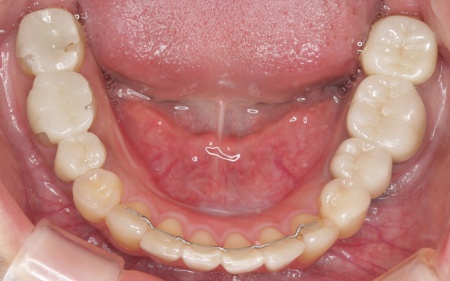

20代女性 ワイヤー矯正で歯並びを整えて虫歯治療やインプラント治療で口腔内全体を改善した症例

診断結果をお伝えしたうえで、以下2つの治療方法を提案しました。 ①歯並びを整えず、必要な部分のみを治療する方法 ②矯正治療で歯並びと噛み合わせの土台を整えたうえで、口腔内全体の治療を行う方法 それぞれのメリット・デメリットをお伝えしたところ、患者様は②の矯正治療を含めた総合的な治療を行う方法を選択されました。 はじめに、歯の表面にブラケットと呼ばれるボタン状の装置を接着し、そこにワイヤーを通して歯を動かすワイヤー矯正を開始しました。治療期間中は定期的に状態を確認し、計画通りに歯が動くよう調整を重ねています。 虫歯が生じている歯に対しては、虫歯部分を丁寧に除去し、歯の形を整えました。その後、被せ物を作製するために型取りを行い、後日完成した被せ物を装着しました。 また、欠損していた左上奥歯1本と左下奥歯1本に対しては、インプラント治療を行います。 すべての治療工程を終えたあと、噛み合わせや見た目、被せ物の使用感に問題がないかなどを確認して、治療を終了しています。 |

治療後